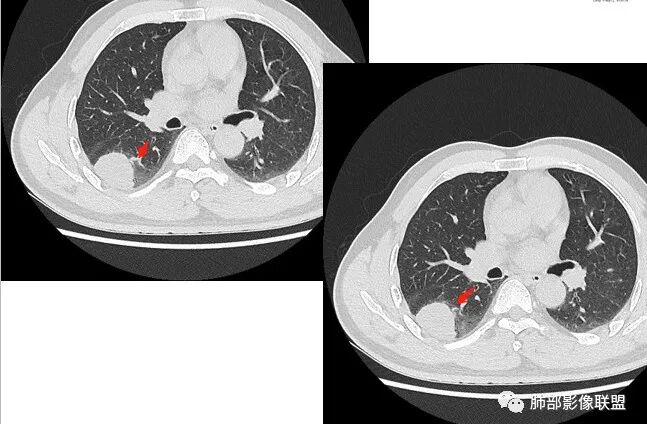

右肺下叶背段胸膜下见团块影,边缘清,其后基底段见一扁平状结节,各见‘’平直及桃尖"征,均轻度强化,右肺上叶背段及中叶外侧段分别少许纤维化灶及部分卫星病灶,一元考虑TB,与隐球菌鉴别!

右肺下叶胸膜下类圆形团块,边缘光滑无毛刺分叶,强化均匀无坏死,另血管旁小结节平直桃尖,上叶小斑片影,考虑结核或者真菌感染。

右肺下叶背段胸膜下见一边缘稍模糊、浅分叶结节灶,密度均匀,似乎轻度均匀强化(具体CT值看不出来),与胸膜锐角相贴,似有平直征和桃尖征。此病灶前内侧还有类似小结节,轻度强化,右肺上叶后段有斑片状稍高密度影:考虑良性病变,炎性结节可能。

晨读,右肺下叶背段胸膜下见肿块影,边缘清晰,未见与气管相连通,右下叶见结节影边缘清晰,两处病变密度均匀,同步不明显强化,中叶外侧段斑点状影,树芽征,考虑1良性病变,结核?隐球菌?2淋巴瘤待除外。

右肺下叶背段胸膜下宽基底团块状占位,浅分叶,边界清晰,胸膜下脂肪间隙清晰,背段支气管管壁似乎增厚,未见明显强化。外侧基底段血管束间结节,边界清晰,亦未见明显强化。中叶外侧段见少许树芽征象。纵隔未见明显肿大淋巴结。我先猜个结核。

男性,49岁,体检发现,右肺下叶背段胸膜下见肿块,边界清楚,边缘光滑,胸膜下脂肪间隙存在,有分叶,无毛刺,均匀强化,内无坏死,右肺下叶血管束间不规则实性结节,边界清楚,无明显强化,中叶少许斑片状高密度影,纵隔未见明显增大淋巴结,考虑良性病变。

2.右肺下叶背段胸膜下块影,边界清楚光整,上下极见磨玻璃晕,未见明显分叶毛刺和棘状突起,未见胸膜凹陷或胸壁侵入。密度均匀,轻度不均匀强化。未见支气管进入。

3.右肺中叶外侧段胸膜下散在小片影,磨玻璃密度为主,边界不清,支气管相关。符合炎性特征!

4.右肺下叶基底段支气管血管束旁小结节影,边界清楚,强化不明显。注意,这结节在“遥远的”基底段。